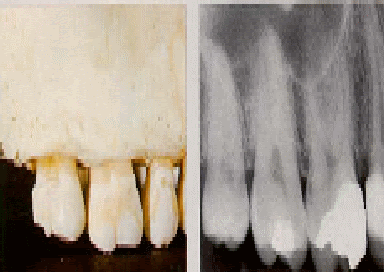

مركز أسنان ابتسامة د/ هشام محمد عبد السلام هو عيادة تخصصية في مجال طب الأسنان. يمكنك التواصل مع الطبيب على الرقم 01007560233.